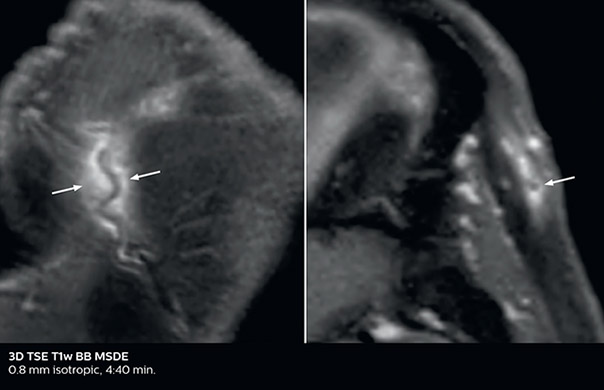

Giant cell arteritis

The 3D TSE T1w black blood MSDE sequence with fat suppression has an isotropic 0.8 mm voxel size and sagittal oblique and axial reformats are made. The images show superficial temporal artery thickening and peri-arterial fat infiltration. The 3D TSE PDw black blood MSDE with fat suppression has 0.55 mm isotropic voxels. The images shows focal involvement of the frontal branch of the superficial temporal artery.